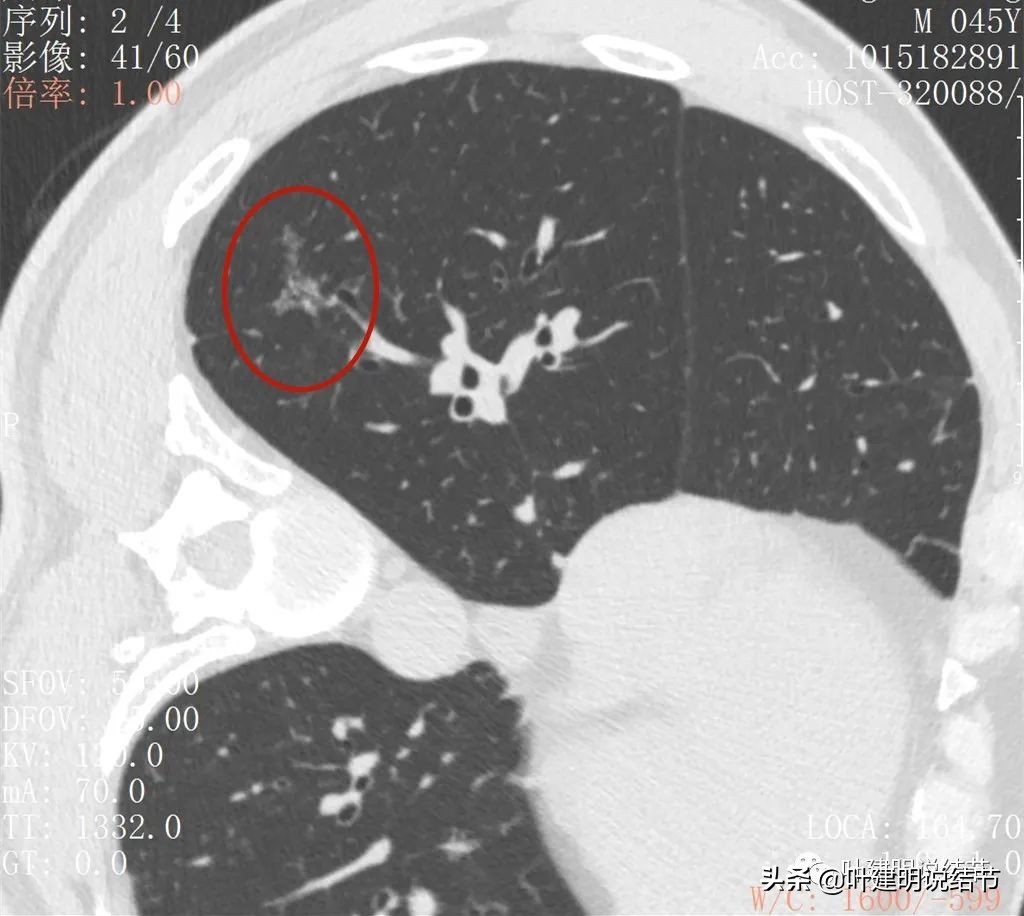

病灶较散在

病灶形态不规则,不是圆形或类圆形

此层见病灶边缘显糊

病灶显模糊,感觉过于散在了些

病灶形散,密度低